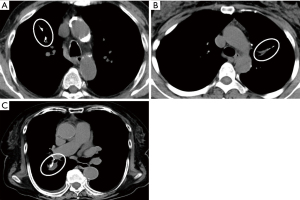

Staple line thickening at the time of the first CT scan after surgery (typically performed 6 months after surgery) was observed in 43 cases (67.2%). Of them, linear thickening was seen in 31 cases (72.1%) and nodular thickening was seen in 12 cases (27.9%). The mean size of thickening was 10.3 mm (range, 4–26 mm). Of these 43 cases, 25 were decreased and 8 were unchanged in shape and size during the course. On the other hand, 10 cases showed a tendency to progress during the follow-up period, of which three cases were linear but increased partially to nodules (Figure 2).

Usuda et al. (16) reported the usefulness of diffusion-weighted magnetic resonance imaging (DWI) for differentiation of suture recurrence and suture granuloma after resection for lung cancer. Mizukami et al. (6) and Mizuno et al. (17) reported differences in morphology. Staple line granuloma shows a smooth marginated mass in contact with the staple line. On the other hand, staple recurrence grows concentrically or radially from the staple line and the edges are irregular. In the present cases, for example, staple recurrence was formed on the edge of the staple line (Figure 2). It is still difficult to distinguish by morphology alone, but in most of the present cases, the granuloma had a smooth margin (Figure 1), which may help in the differentiation.